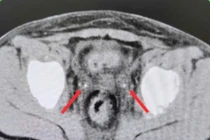

Theo đó, ngày 01/03/2026, Bệnh nhi N.T.L nhập viện trong tình trạng đau bụng vùng hố chậu phải tăng dần, kèm theo biểu hiện sốt nhẹ và buồn nôn. Qua thăm khám lâm sàng và thực hiện các xét nghiệm cận lâm sàng (siêu âm bụng, xét nghiệm máu), các bác sĩ đã chẩn đoán xác định viêm ruột thừa cấp.

BSCK I Trần Quốc Vĩnh phân tích, chẩn đoán viêm ruột thừa ở trẻ em khá phức tạp, đặc biệt ở trẻ nhỏ. Việc khám và theo dõi diễn tiến lâm sàng là yếu tố quan trọng trong chẩn đoán và quyết định phẫu thuật. Trong 90% trường hợp, ruột thừa nằm ở hố chậu phải.